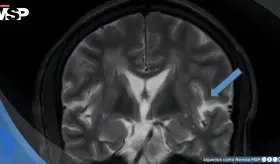

Un dolor de cabeza que empeora al estar de pie y mejora al acostarse es una señal de alerta. Esta cefalea ortostática fue la clave para identificar que no se trataba de migraña, sinusitis ni cambios hormonales, sino de un problema con la presión del líquido que rodea el cerebro.